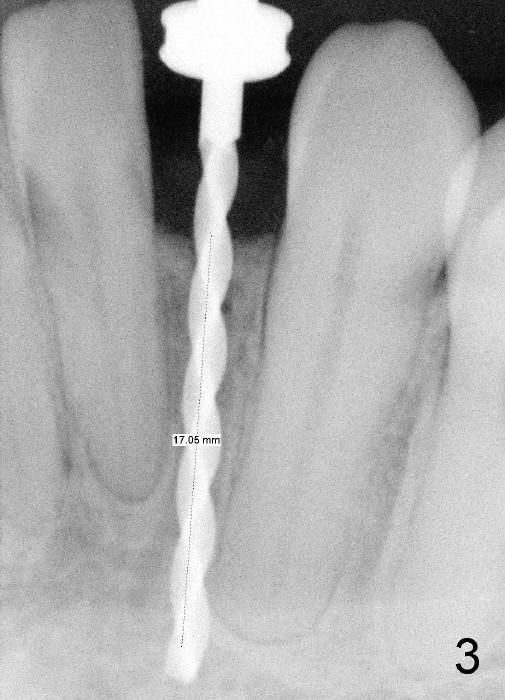

Informed consent is obtained with emphasis of potential damage to the neighboring roots.  Two PAs have to be taken with the first pilot drill (1.5 mm) in place for determination of initial trajectory (Fig.2,3).  Osteotomy is enlarged coronally with 2 mm pilot drill.  Finally a 3x17 mm one piece implant is placed with primary stability, determined tactilely (Fig.4).  Immediate provisional is fabricated.  To avoid micromovement, the immediate provisional (Fig.5 P) is bonded to the neighboring teeth with composite (*); it is further fixed in place with a lingual retainer (Fig.6 arrowhead).